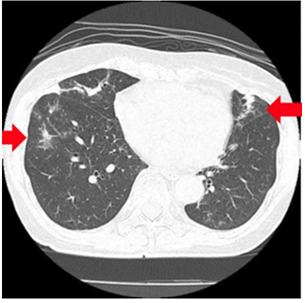

肺真菌症

体力の落ちた方は、真菌(カビの仲間)に感染する場合があります。

咳、胸痛、血痰などの症状が出ます。